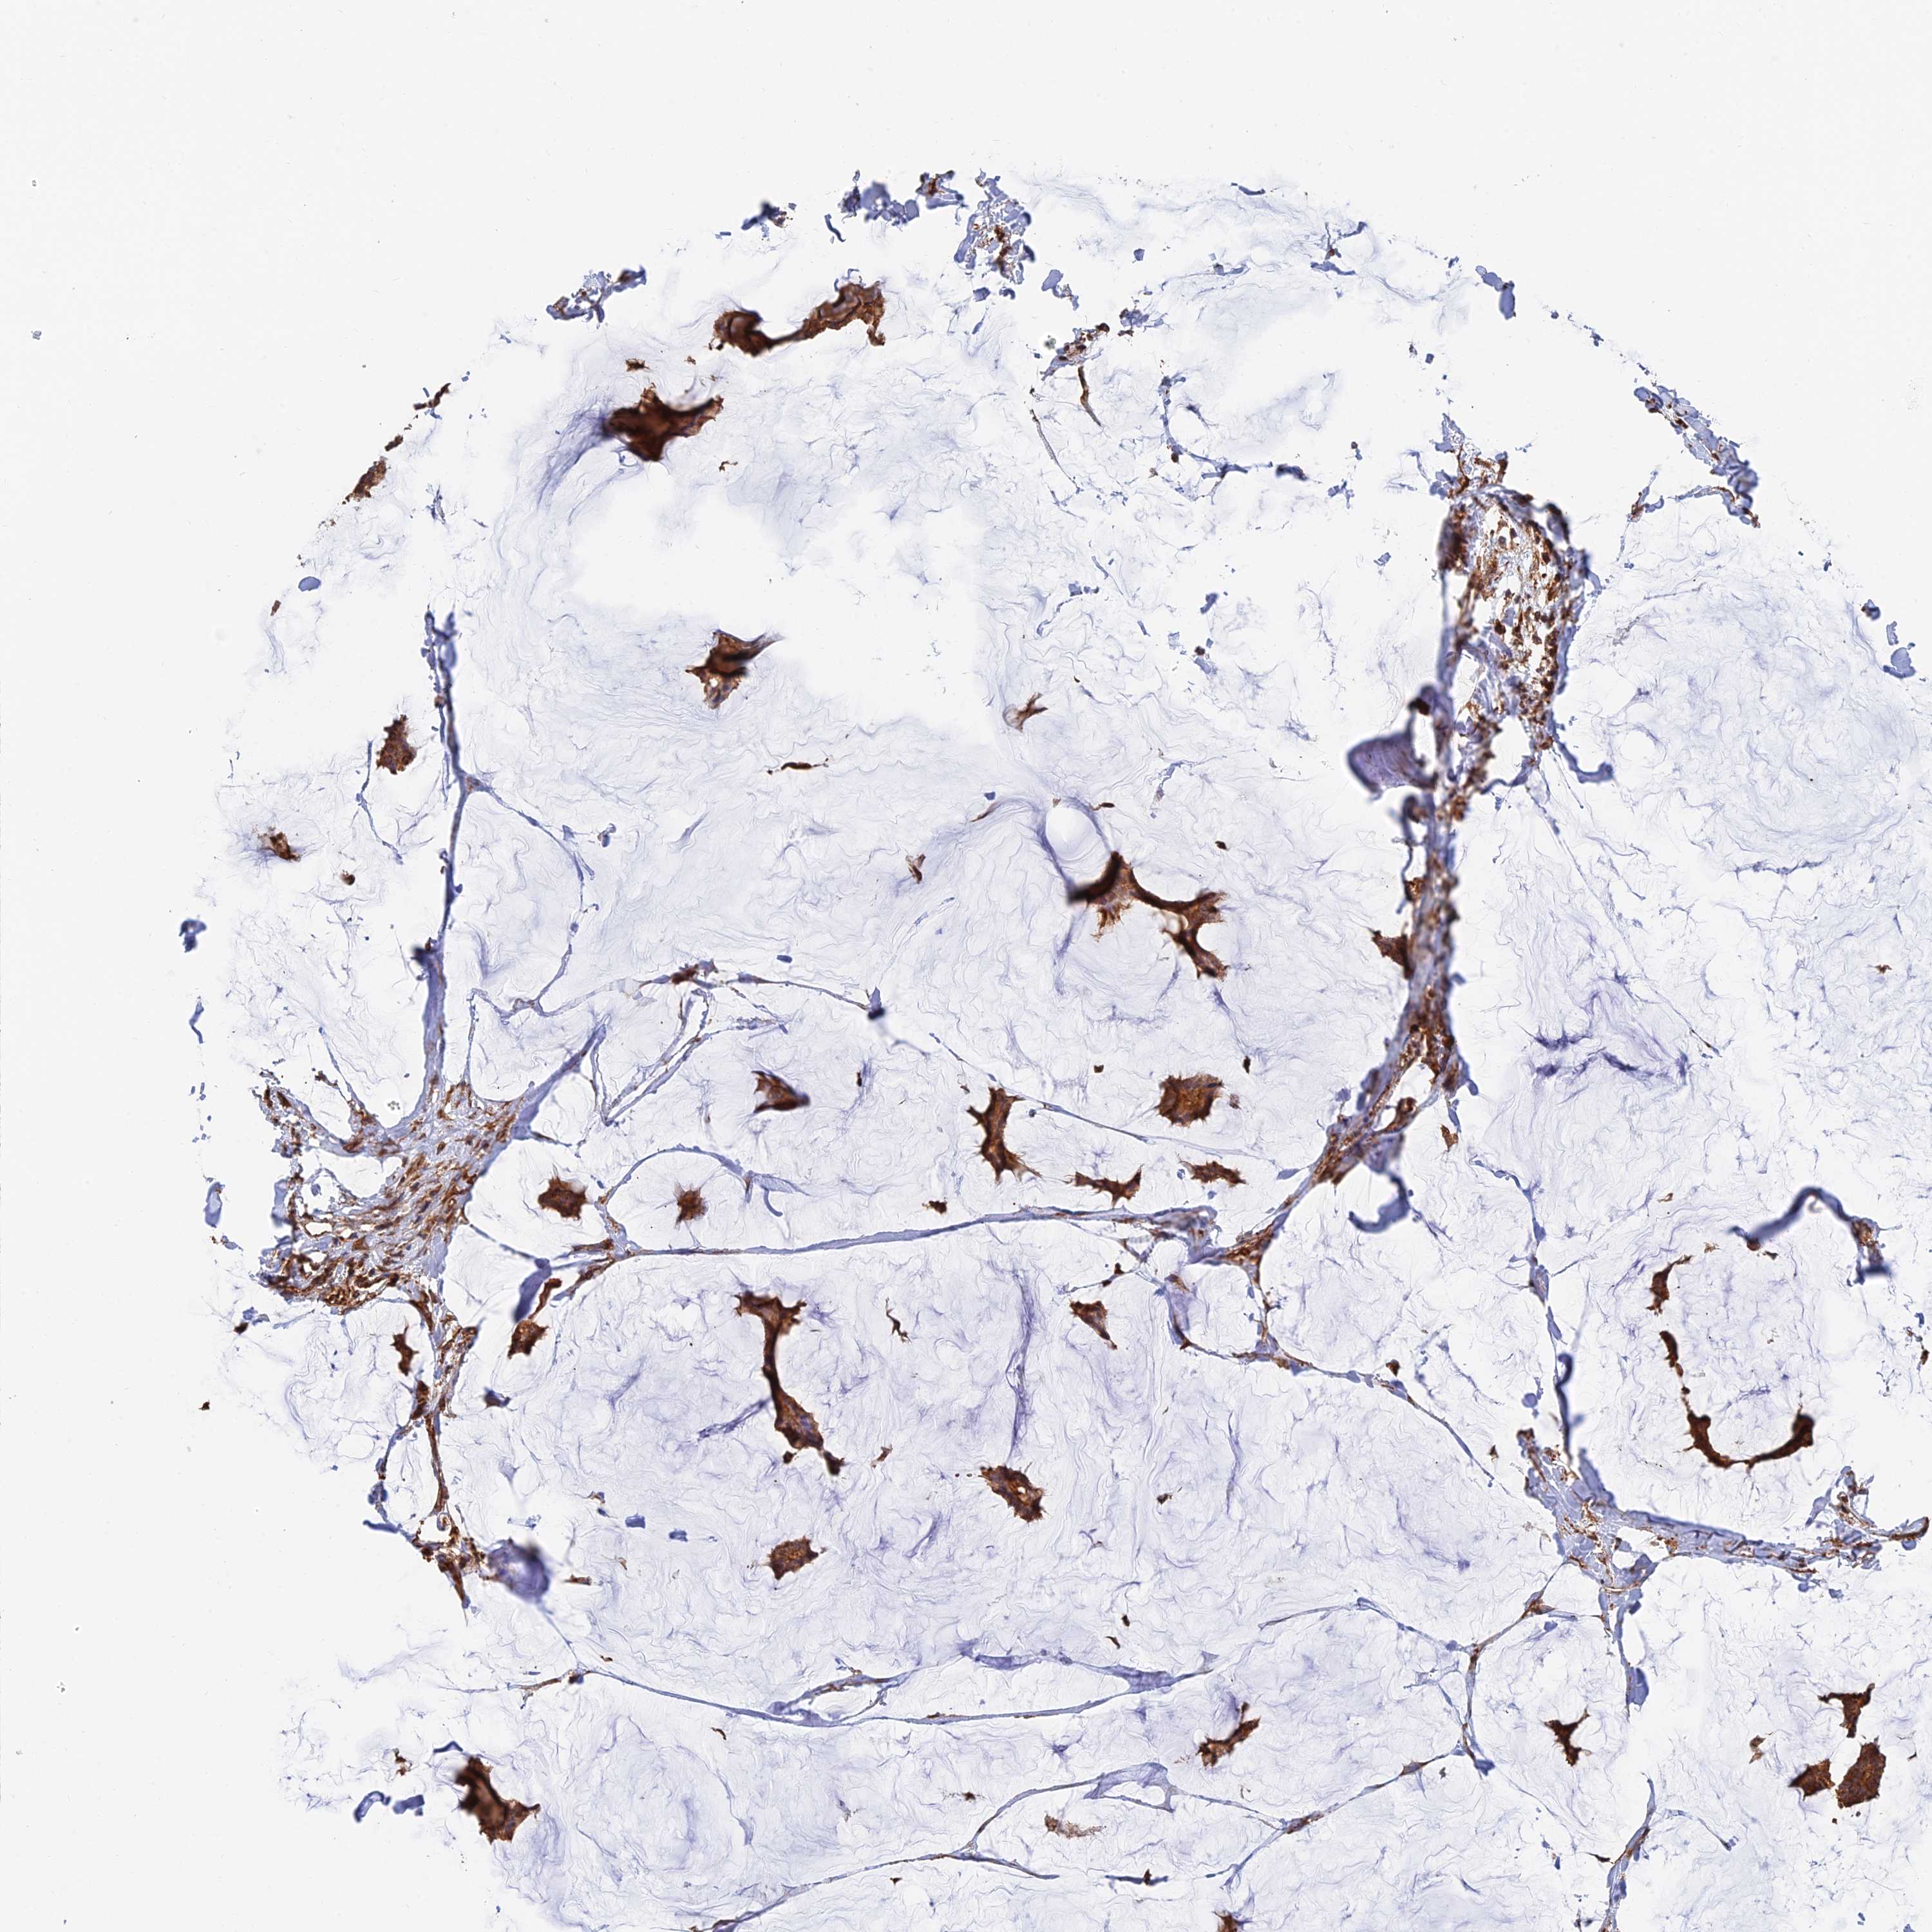

BRCA TCGA BRCA VALIDATION PROTEIN EXPRESSION

ANTIBODIES

AND

VALIDATION